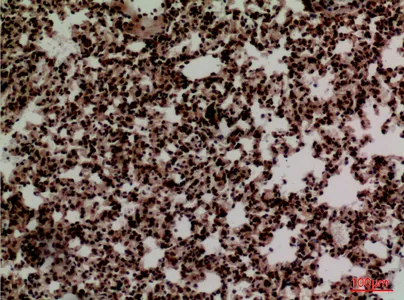

FOXP1 Rabbit Polyclonal Antibody

Cat: APRab11113

Size1:50μl Price1:$118

Size2:100μl Price2:$220

Size3:500μl Price3:$980

Size2:100μl Price2:$220

Size3:500μl Price3:$980